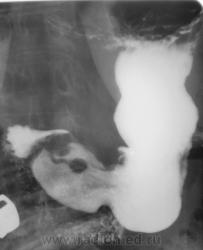

1. Аденоидные полипы в антральном отд. желудка.

Во всяком случае полиповидное выпячивание в антруме налицо, но думаю оно подслизистое... А варикоз - явно не виден, есть в кардии складка небольших размеров, но явно в глаза она не бросается, хотя складки везде толстоваты...

полиповидные образования в антральном отделе +грыжа ПОД

Смею предположить (с учетом наличия + тени кардии желудка по верхне-медиальной стенке, некоторого удлинения и выпрямления кардиального канала, неровности контуров) кардио-эзофагеальный рак без стеноза. В антруме - полипы. Вряд ли подслизистые образования, такие на вершине складок не образуются.

На снимке который поместил Анатолий Владимирович, м.б. или ГПОД (кардиальная) или ахалазия пищевода,при ней газовый пузырь отсутствует или уменьшен в размере. А м.б. и c-r пищеводно-желудочного перехода.

Наблюдение архивное. Я этот снимок привел как типичный пример ампулы пищевода, нормальной, в горизонтальном положении тела, которую наша братия, почти поголовно принимает за грыжу пищеводного отверстия, и соответственно с нашей подачи хирурги пытаются это оперировать...

1.о варикозе вен н\трети пищевода стоит подумать, весьма коварная вещь;

2. полипы препилорического отдела не вызывают сомнения, но что тут интересно - картинка то меняется, периодически крупный дефект выполнения как бы исчезает...но появляется в основании луковицы - сдается мне - это полип на длинной ножке, вот и гуляет он через привратник туда-сюда, вспоминайте - симптом "собачки на цепочке"...

Да, данные ФГДС подтвердили наличие полипов в препилорической части, один действительно - "гулящий" - на длинной ножке.